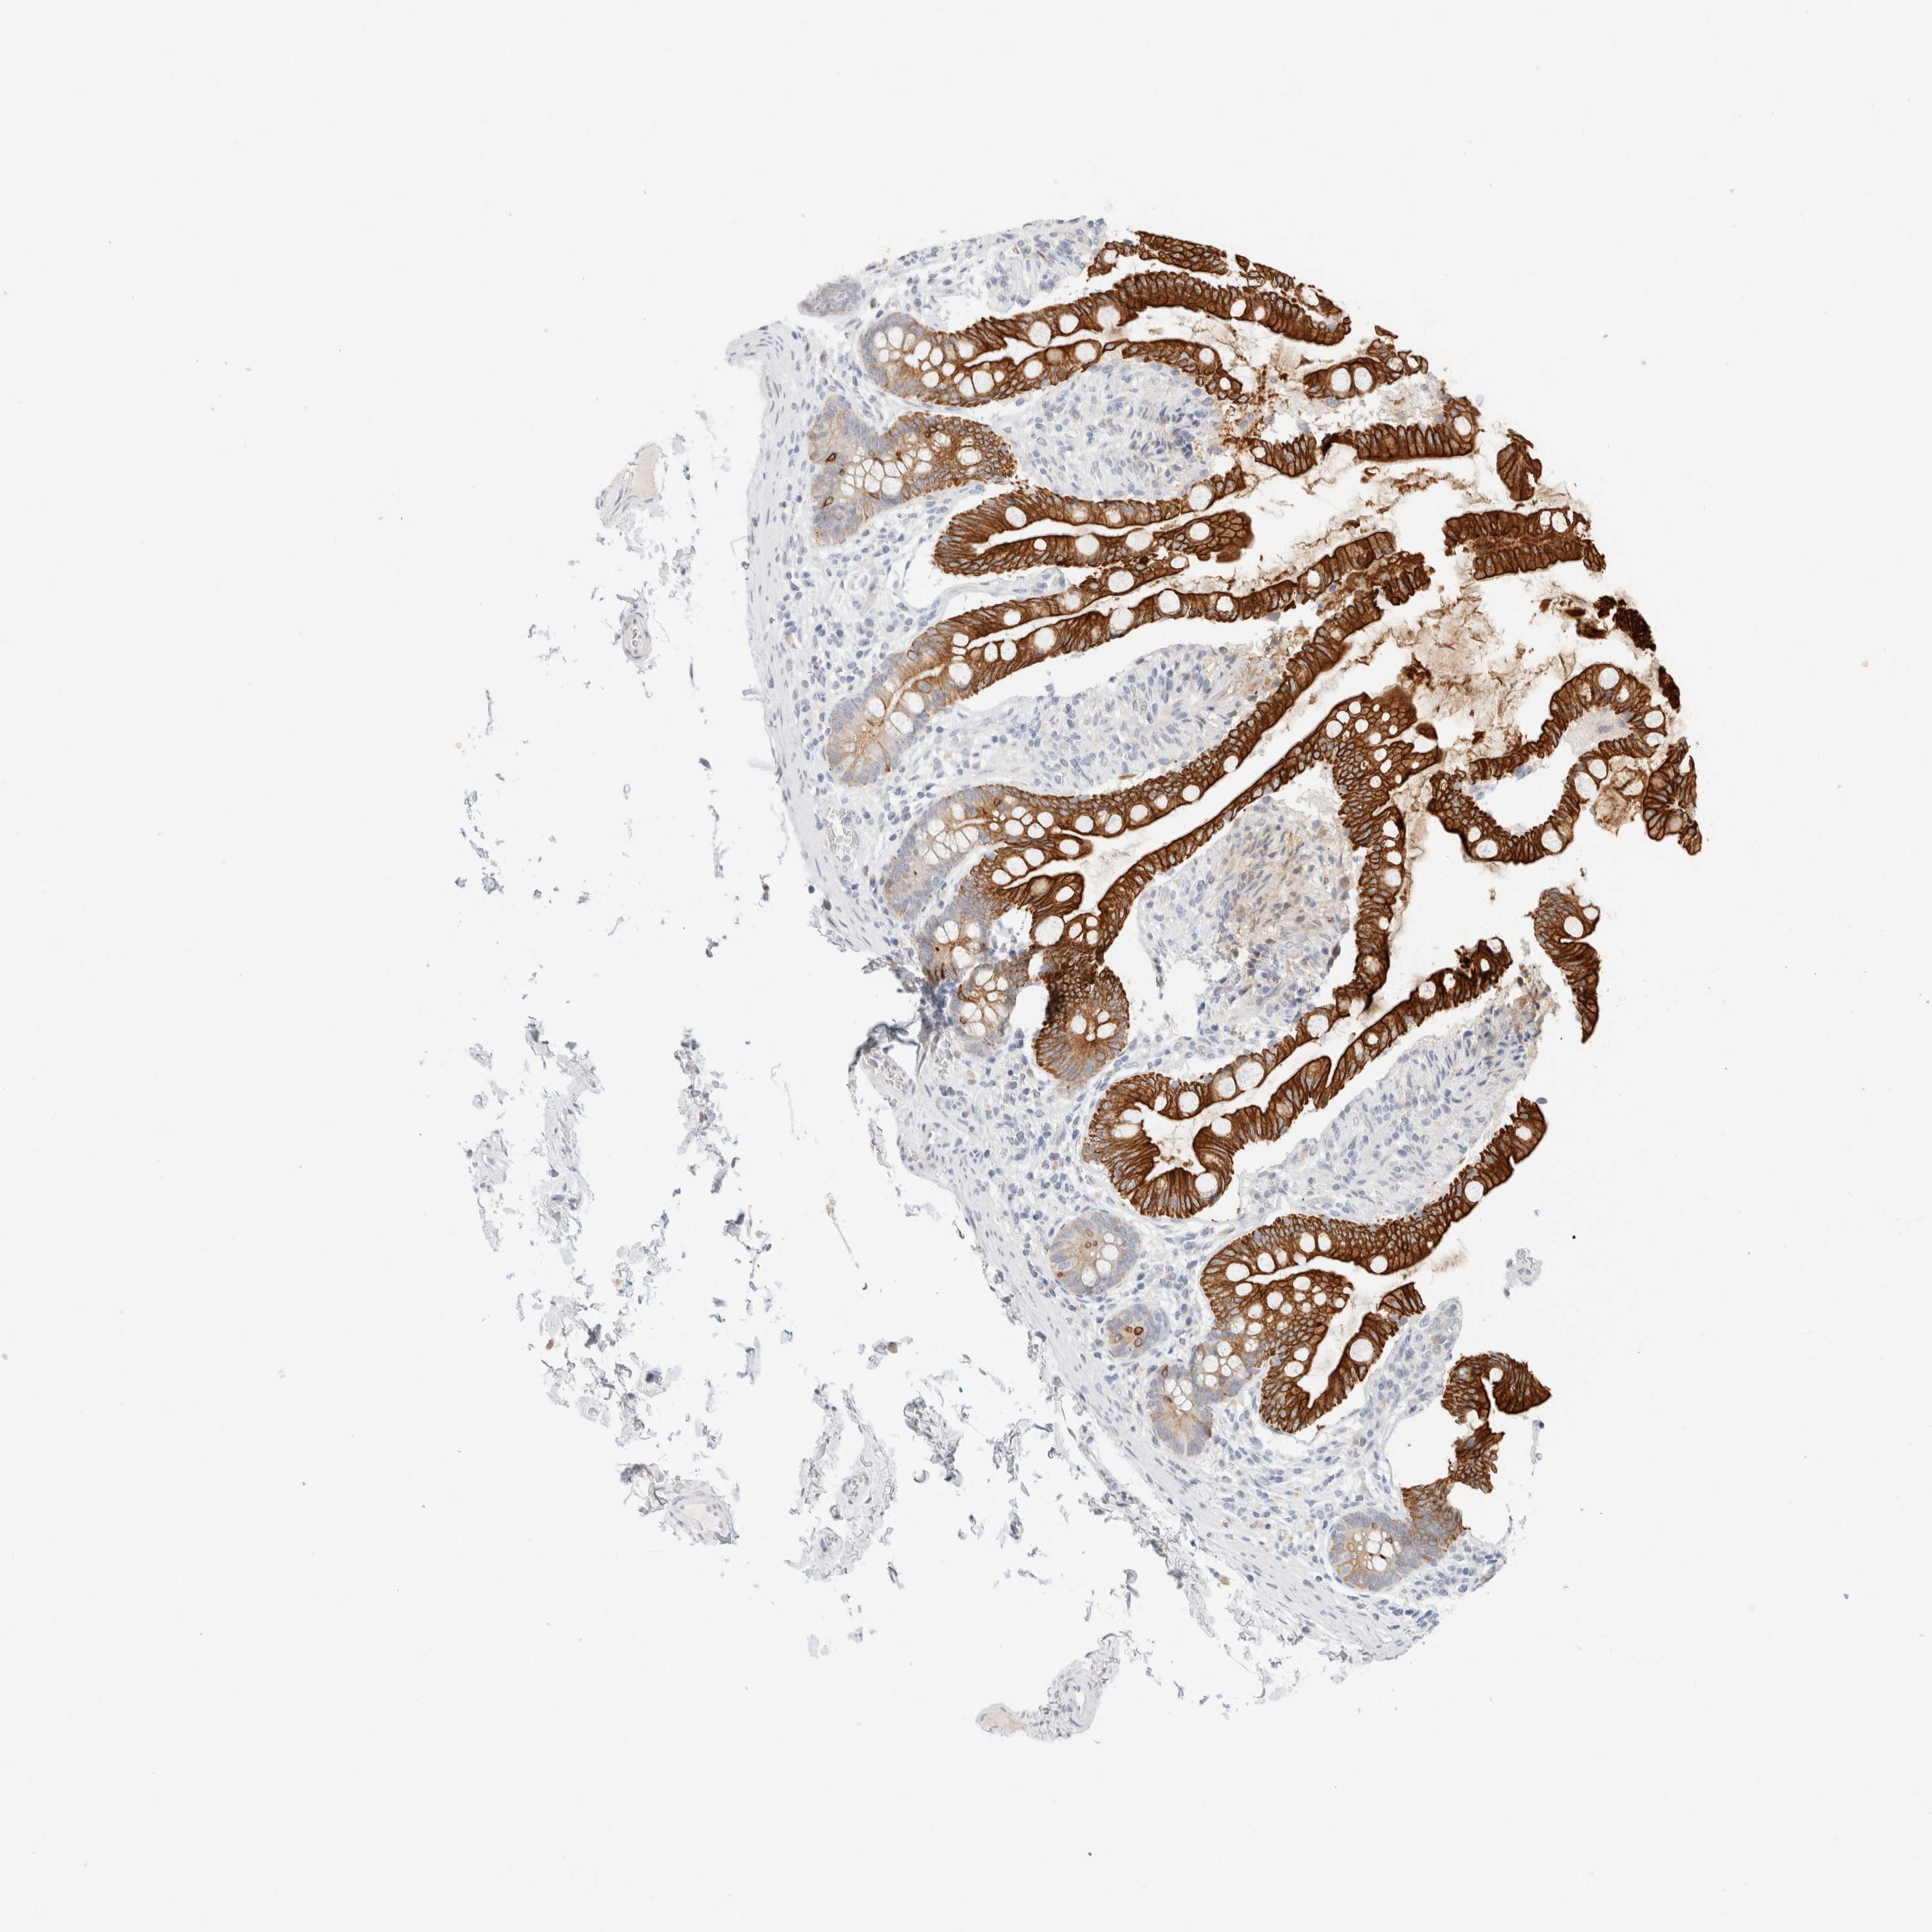

SMALL INTESTINE - Antibody stainingi

Antibody staining in the annotated cell types in the current human tissue is reported as not detected, low, medium, or high, based on conventional immunohistochemistry profiling in selected tissues. This score is based on the combination of the staining intensity and fraction of stained cells.

Each image is clickable and will lead to virtual microscopy that enables deeper exploration of all samples and also displays staining intensity scores, fraction scores and subcellular localization as well as patient and tissue information for each sample.

Antibody HPA024309Antibody HPA024684Antibody HPA027236Antibody CAB000032

Endocrine cells ---High

Enterocytes ---High

Enterocytes - Gradient ---Ascending

Enterocytes - Microvilli ---High

Glandular cells HighHighHigh-

Goblet cells ---High

Paneth cells ---Not detected